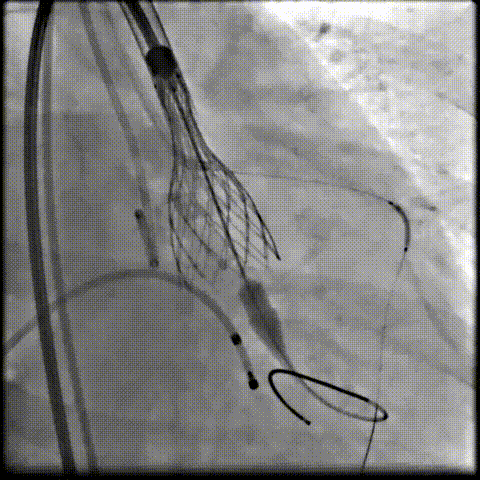

术中影像

根部造影可见返流;20mm球囊预扩,LCA灌注缝隙狭小

预置LCA保护;第一次释放,

团状钙化挤压导致瓣膜(AV23)少量下滑

回收后重新定位,第二次释放,

瓣膜(AV23)深度仍未达到最佳预期

完全回收,第三次定位释放,瓣膜(AV23)位置良好

瓣膜工作位释放“烟囱支架”;

瓣膜(AV23)完全释放后,“烟囱支架”后扩

最终造影,“烟囱支架”显影清晰,瓣膜形态及LCA灌注良好